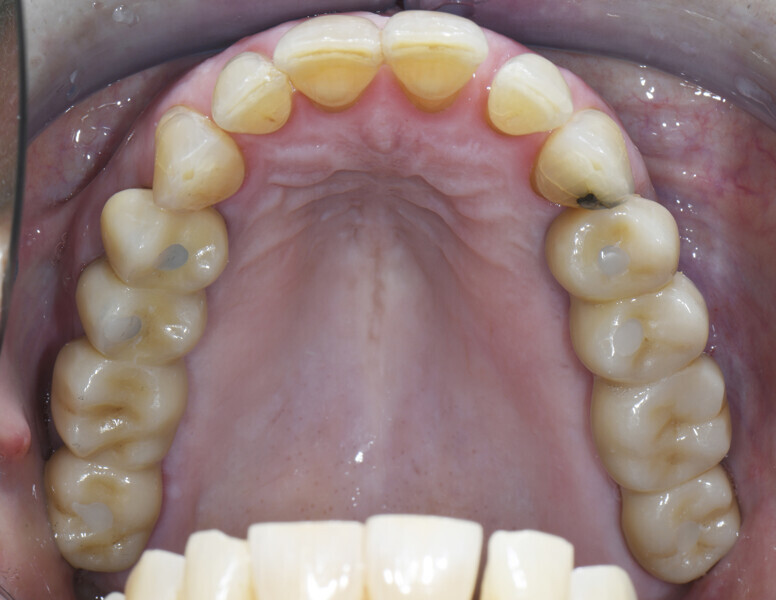

Owing to chronic periodontal disease, the 65-year-old female patient had lost premolars and molars in the maxillary arch (Fig. 1). It was decided to perform her treatment with dental implants.

PrimeTaper EV implants (Dentsply Sirona) were placed in the maxillary premolar and molar positions (Fig. 2). MultiBase Abutments EV (Dentsply Sirona) were positioned and temporary screw-retained bridges loaded immediately (Figs. 3 & 4). To ensure that the implant positions were correct, a postoperative radiograph was performed (Fig. 5).